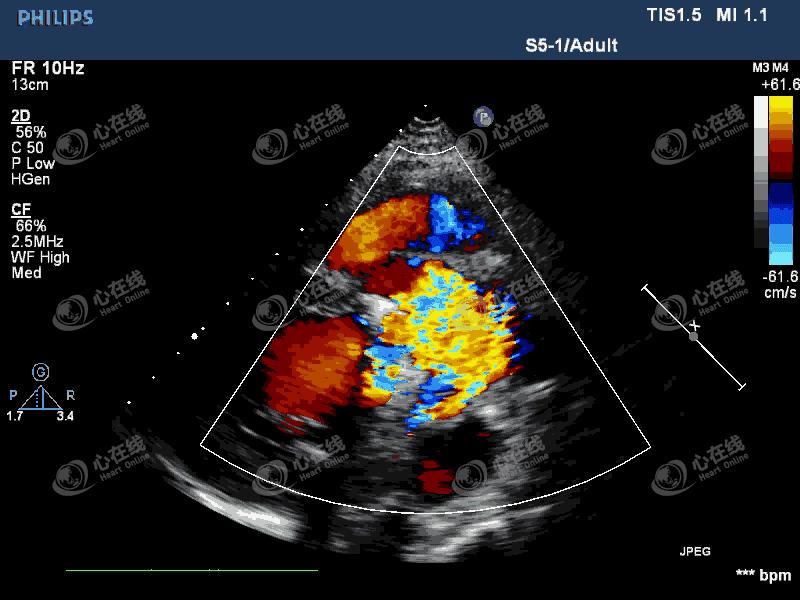

【超声心动图】

图2 左室长轴切面:彩色多普勒示,机械瓣瓣环外侧可见中量血流信号进入左室,另可见机械瓣中心性反流信号。主动脉根部膜样回声破口处可见血流信号,来自主动脉,并穿梭于该无回声区内。